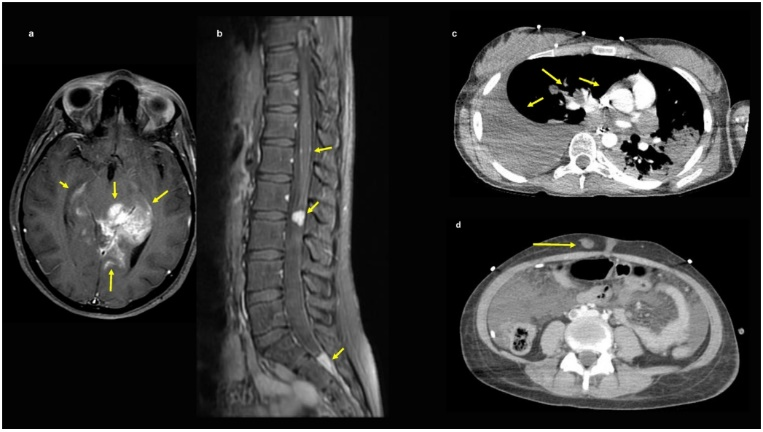

图2. H3K27M突变型弥漫性中线胶质瘤伴脑外转移的影像学特征。17岁女性,头痛伴复视2周。颅脑MRI显示累及左侧海马延伸至左侧中脑后部的强化病变,伴颅内广泛LMD(图3a)。脊柱MRI提示弥散性病变(图3b)。脑组织活检确诊DMG伴H3K27M突变pHGG。脑肿瘤NSG结果为H3F3A(p.K28M)和TP53突变(表1)。放疗后7周,患者出现呼吸短促,胸部CT发现大量胸腔积液(图3c)。胸部、腹部和骨盆CT示纵隔和肺门淋巴结肿大,肺和胸膜多灶性结节,多发低强化肝脏病变,大网膜脂肪束与转移性病变一致(图3c、d)。胸腔积液检查为88%的恶性细胞,腹壁软组织病变活检(图3d)和皮肤活检证实为转移性H3K27M突变型pHGG。

图3. H3K27M突变型弥漫性中线胶质瘤伴脑外转移的影像学特征。